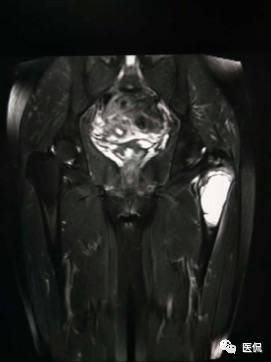

影像资料:

(3)MRI ABC的特征为鼓囊状的膨胀性破坏,呈单囊或由低信号的间隔分隔成大小不等的多囊。因血细胞和血浆的分离和沉淀,囊内可见液-液平面。在T2WI上,液面上层为高信号,下层为低信号;T1WI上则相反,上层为低信号,下层为偏高信号。液-液平面是ABC较特征的征象。增强检查低信号的纤维间隔呈环形强化。继发性动脉瘤样骨囊肿可在其原发病灶内有液-液平。

【诊断要点】发生于青少年长骨干骺端偏心膨胀的溶骨性病变,MRI检查病灶内见有液-液平征象时应首先考虑为动脉瘤样骨囊肿。